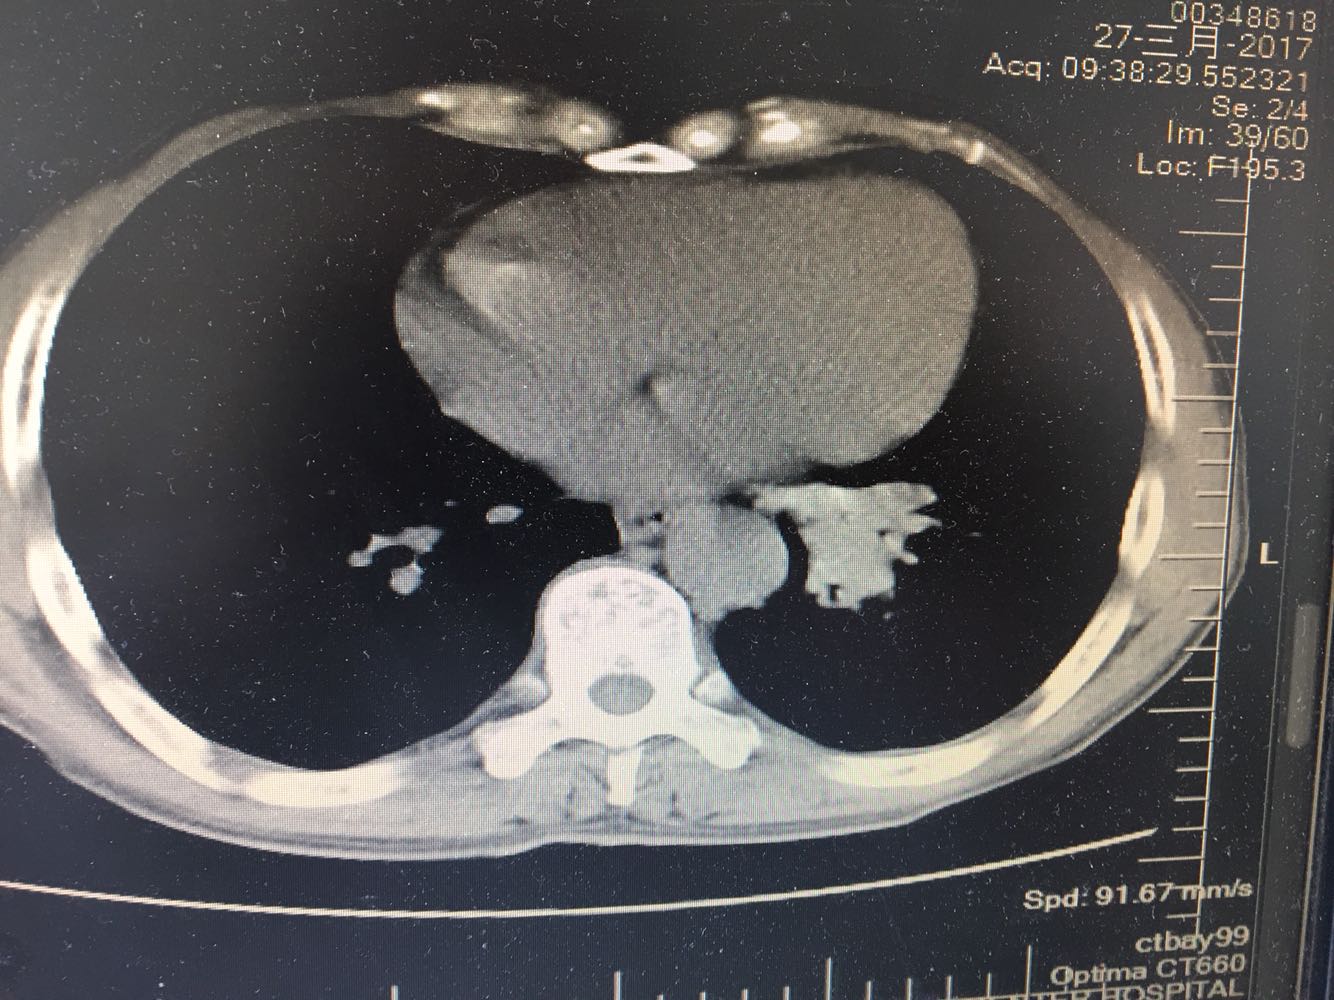

左肺下叶鳞癌

男,63岁,咳嗽1个月入院,患者自述1个月前无诱因咳嗽,阵发性干咳,无痰,时有血丝,无发热,左胸痛,活动后气短,静滴头孢13天无好转,门诊查肺CT后以 肺占位收入我科,病来饮食睡眠可,体重明显下降。既往疝气术后1年,吸烟史30年,每日1包。

左肺癌

左肺中央型肺癌,是否可以手术,还是化疗,放疗,靶向治疗?